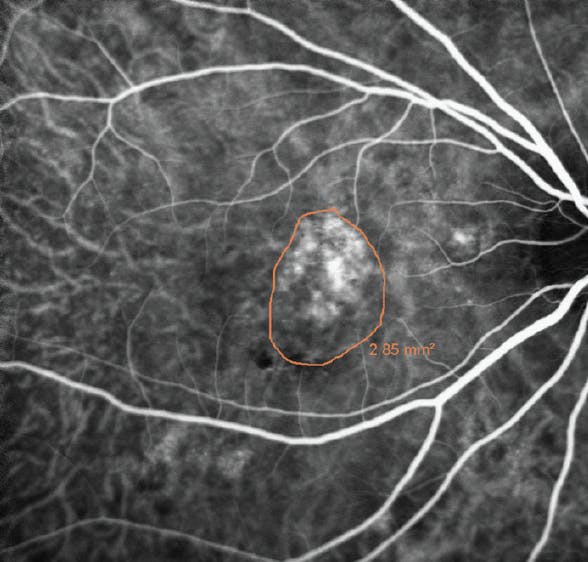

For eyes with PCV, the target of PDT is based on the location of polypoidal neovascular lesions on ICGA. The treatment spot is limited to a diameter matching the greatest linear dimension of the polypoidal neovascular lesion or a localized 300 µm border around the lesion (Figure 2). The combination of PDT and anti-VEGF injection can markedly decrease the need for injections with good visual outcomes and can result in a significant benefit in eyes demonstrating anti-VEGF resistance (Figure 3).

<p>Figure 2. ICGA shows polypoidal vascular complex with the target (orange outline) around the lesion. The PDT beam is set at the greatest linear dimension of the lesion or 300 µm larger.</p>

Figure 2. ICGA shows polypoidal vascular complex with the target (orange outline) around the lesion. The PDT beam is set at the greatest linear dimension of the lesion or 300 µm larger.